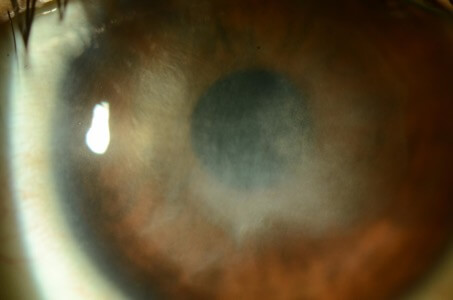

角膜血管增生

照片由香港理工大學眼科視光學院提供